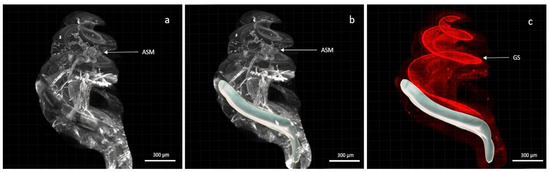

2.4. Light-Sheet Microscopy

2.5. Three-Dimensional (3D) Analysis